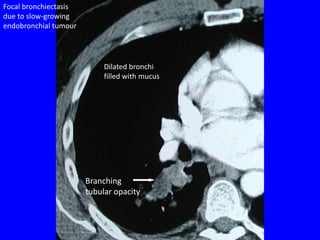

Focal bronchiectasis

due to slow-growing

endobronchial tumour

Dilated bronchi

filled with mucus

Branching

tubular opacity

instead of air due to

proximal obstruction